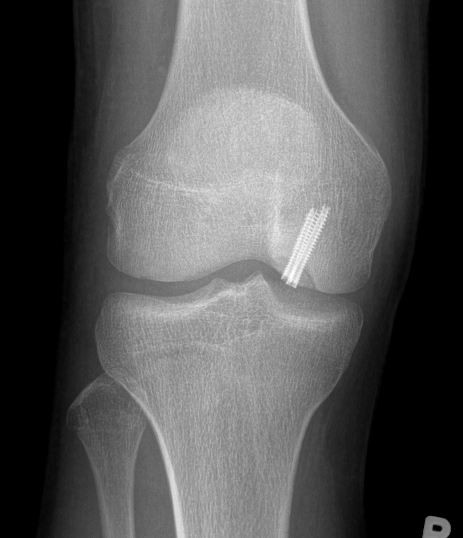

MFC unstable OCD

LFC unstable OCD